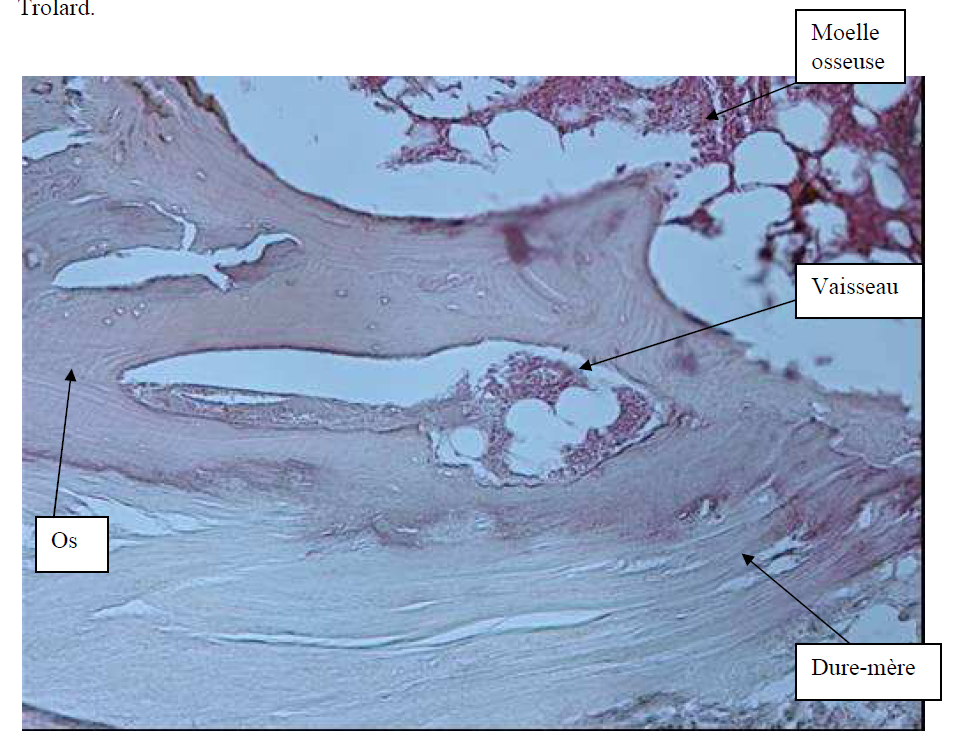

Photo INSERTIONS DE LA DURE-MERE SUR LE RACHIS Une anatomie redécouverte 32

Photo INSERTIONS DE LA DURE-MERE SUR LE RACHIS Une anatomie redécouverte 33